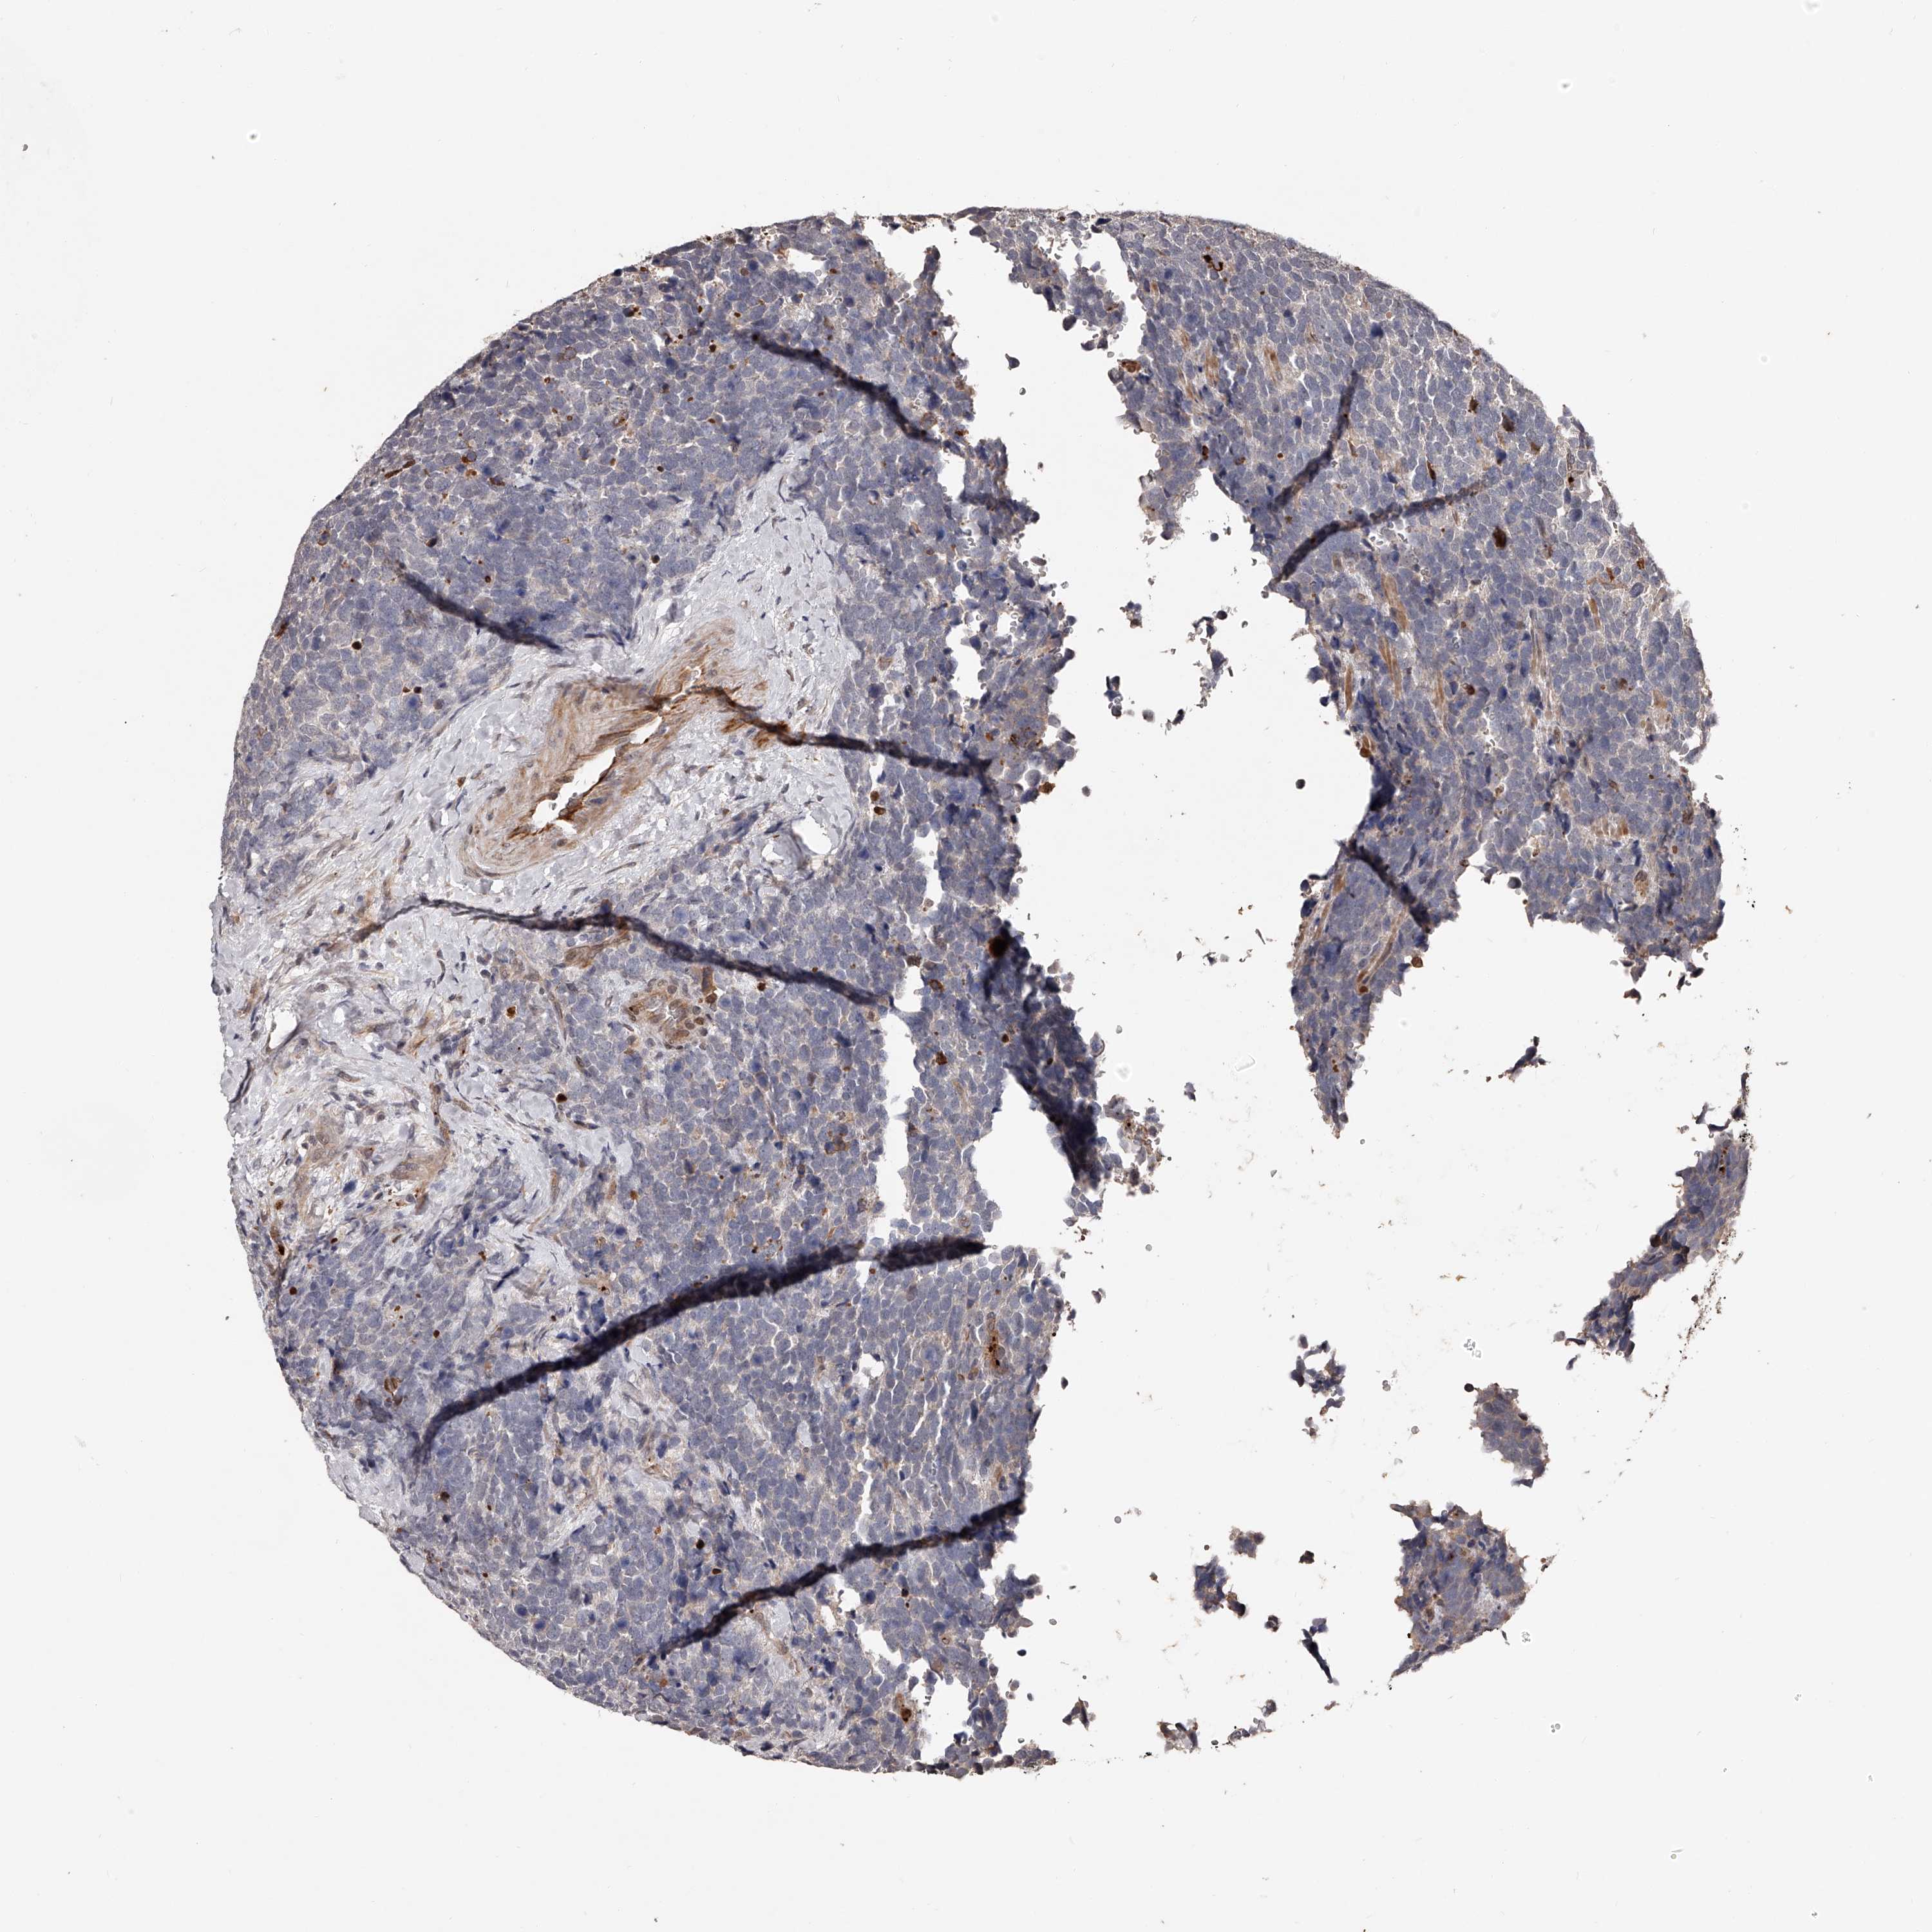

UROTHELIAL CANCER - Protein expressioni

A mouse-over function shows sample information and annotation data. Click on an image to view it in a full screen mode. Samples can be filtered based on level of antibody staining by selecting one or several of the following categories: high, medium, low and not detected. The assay and annotation is described here.

Note that samples used for immunohistochemistry by the Human Protein Atlas do not correspond to samples in the TCGA dataset.

Antibody stainingi

Antibody staining in the annotated cell types in the current human tissue is reported as not detected, low, medium, or high, based on conventional immunohistochemistry profiling in selected tissues. This score is based on the combination of the staining intensity and fraction of stained cells.

Each image is clickable and will lead to virtual microscopy that enables deeper exploration of all samples and also displays staining intensity scores, fraction scores and subcellular localization as well as patient and tissue information for each sample.

Antibody HPA019879

Antibody HPA020134

Antibody HPA029468

Staining

High

Medium

Low

Not detected

Intensity

Strong

Moderate

Weak

Negative

Quantity

>75%

75%-25%

<25%

None

Location

Nuclear

Cytoplasmic/membranous

Cytoplasmic/membranous,nuclear

Urothelial carcinoma, Low grade

Urothelial carcinoma, High grade